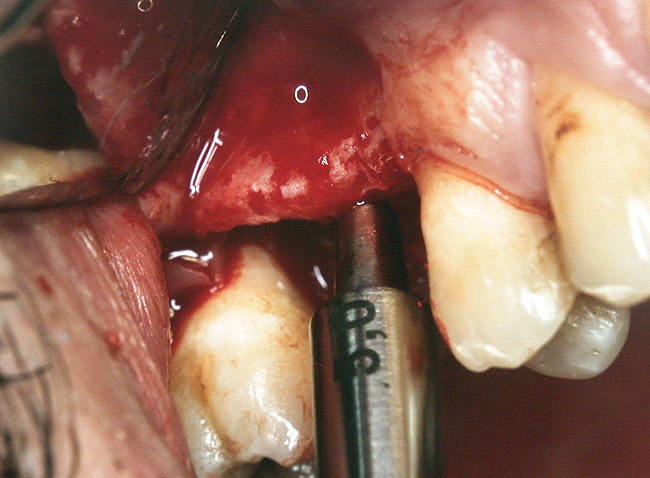

A full-thickness mucoperiosteal flap was raised, and alternating osteotomes were used to prepare the implant site. After achieving a length of 7 mm (Figure 7A and Figure 7B), heterologous bone graft was implanted and the osteotome sequence was repeated. The implant showed primary stability.

Figure 7a  Alternating osteotomes with variable conicity used to perform the alveolar remodeling in the area of tooth No. 15.

Figure 7a

Figure 7b  Alternating osteotomes with variable conicity used to perform the alveolar remodeling in the area of tooth No. 15.

Figure 7b